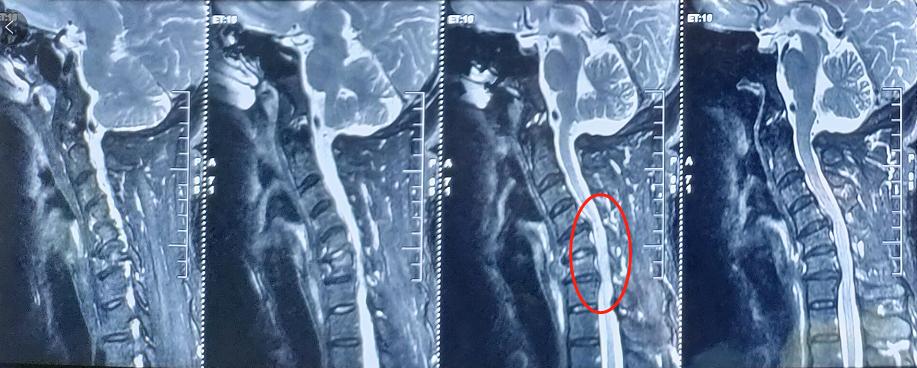

廖博主任接诊后,结合王先生的影像学资料、症状表现以及其他检查结果,最终确诊他为“平山病”。由于患者颈椎严重反曲,且脊髓腹侧受到压迫,廖博主任建议尽快进行手术治疗。

术前影像学资料: